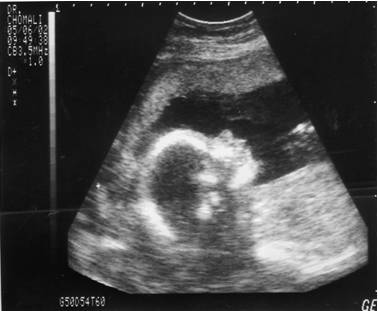

También me llamó la atención que, en los establecimientos acreditados donde practican abortos, no se les permita a las madres ver la ecografía de sus hijos. Incluso bajan el volumen del ecógrafo para que ellas no puedan oír los latidos del corazón del feto. Si esto es así, como parece que es, resulta obvio que están ocultando la verdad, toda la verdad, a las mujeres que, por voluntad propia o por presiones, acceden a someterse a la singular intervención que consiste en expulsar de su útero a su propio hijo causándole la muerte.